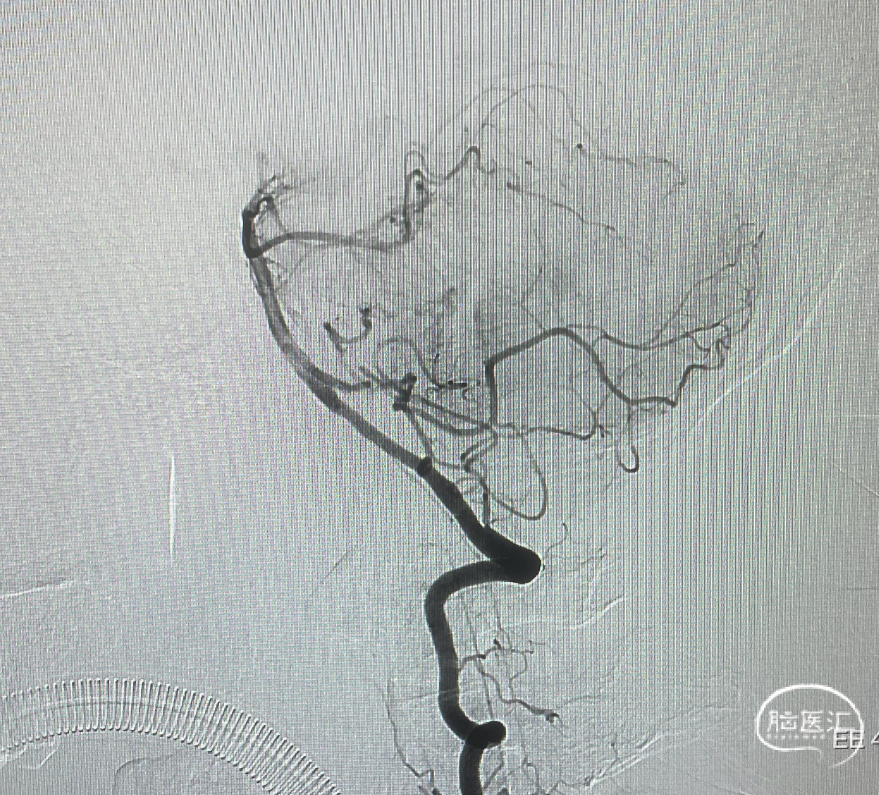

造影显示瘘口不显影,无静脉早显。

双侧颈外、颈内动脉正侧位造影瘘口均不显影

双侧椎动脉造影未见瘘口显影,可见广泛皮层静脉瘀滞

Onyx胶铸型显示瘘口形态。

右侧颈内动脉造影未见瘘口显影及静脉早显

右侧颈外动脉造影未见瘘口显影及静脉早显

左侧椎动脉造影未见瘘口显影及静脉早显